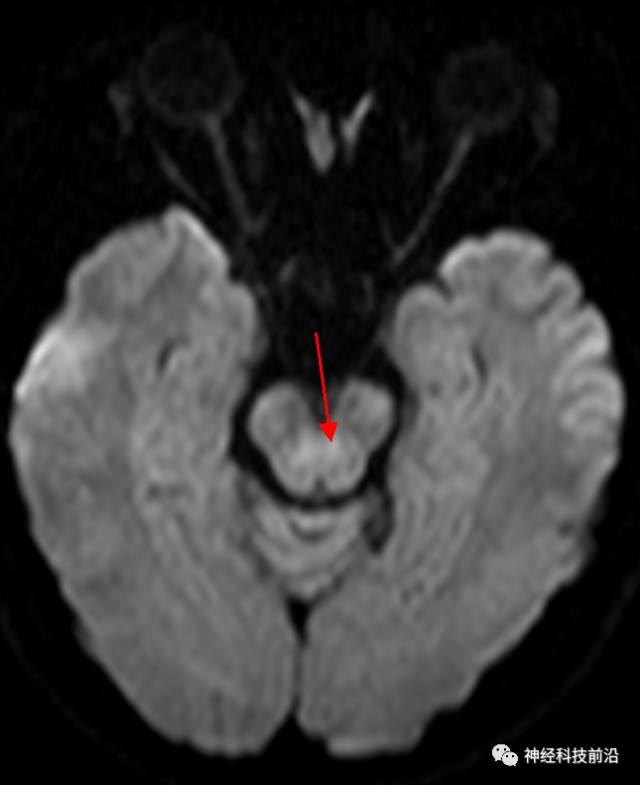

DWI脑干和内囊后肢经常显示为高信号,它是什么纤维束呢?皮质脊髓束?

脑干内高信号为一近环形纤维束,其作用尚待研究。